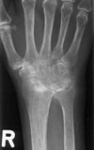

Weitere künstliche Gelenke

​Eine Versorgung mit Kunstgelenken ist auch bei Arthrosen anderer Gelenke möglich. Zu nennen sind hier insbesondere das Ellenbogengelenk, das obere Sprunggelenk, das Handgelenk, das Daumensattelgelenk sowie die Grundgelenke der Finger. Die Indikationsstellung für eine endoprothetische Versorgung der genannten Gelenke sollte ebenfalls im Rahmen einer ambulanten Vorstellung geklärt werden.

Arthrose Ellenbogengelenk Endoprothese SprunggelenkArthrose Handgelenk Arthrose Sprunggelenk

Endoprothese Ellenbogengelenk Endoprothese DaumensattelgelenkEndoprothese FingergelenkEndoprothese Handgelenk